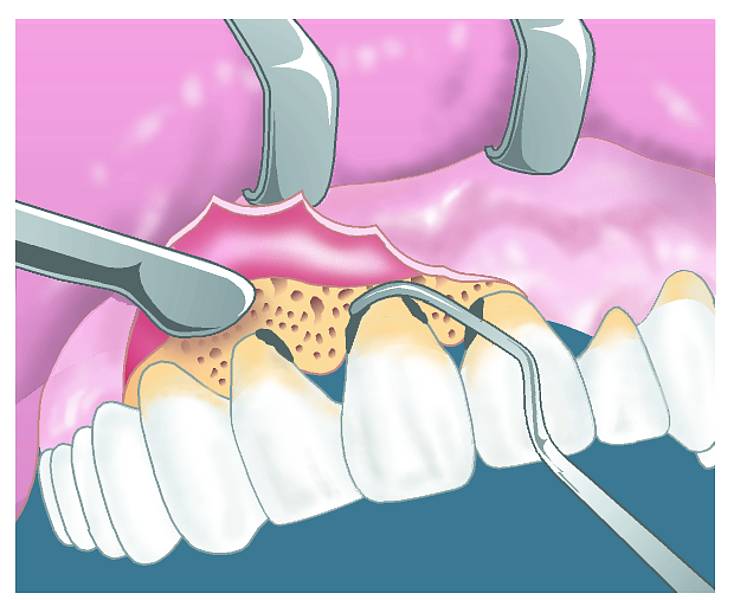

Doenças periodontais

As doenças periodontais afetam as gengivas e o tecido de suporte dos dentes. Quando não tratadas, essas enfermidades podem se expandir até a polpa dentária, causando infecções graves que podem comprometer a estrutura do dente.